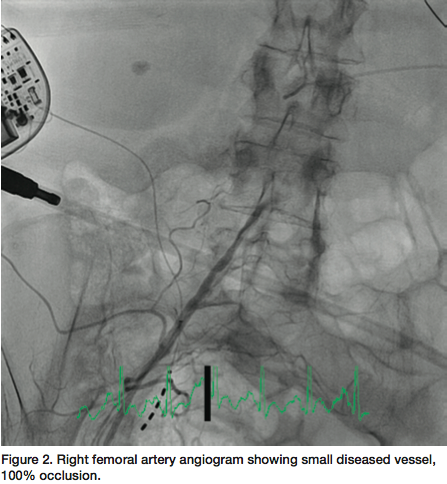

Little did I anticipate that this patient would have the worst peripheral vascular and coronary artery disease I had seen in ten years. The procedure began from the femoral approach since she had bilateral wrist contractures and no pulses. Ultrasound-guided femoral artery access was used since there were no palpable femoral pulses. After an hour of attempts for access, we found that the right iliac artery was 100% occluded and the left femoral and iliac arteries were diffusely diseased, with serial 90% lesions to the aortic junction (Figures 2-3). We were able to pass 5 French catheters to the coronary ostia and found that both the left and right